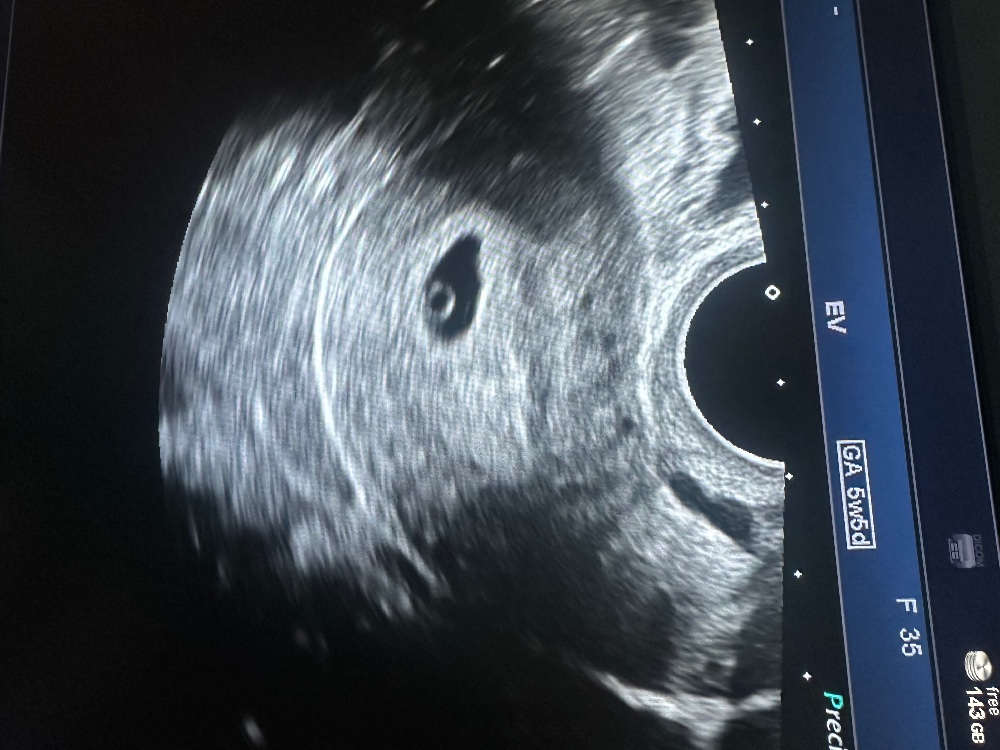

Предыдущее узи было чуть больше недели назад , там только ПЯ и ЖМ было видно, поэтому я рассчитывала что сейчас и эмбриона увидят и СБ как бы должно бы быть.

А узист мне и говорит: вот вижу у вас эмбрион на 6 недель развитием, но к нему нет кровотока, сердцебиения тоже нет.

И написал мне в заключении ,что определяется один неживой эмбрион, замершая беременность.🤯

На приёме гинеколог естественно делает узи и говорит :" сильный тонус очень, но странно что он кровотока не увидел, я вот вижу."

Потом ещё крутит-вертит датчик и говорит: "я вижу сердцебиение , смотри", а на экране чётко и равномерно пульсирующий эмбрион (маленький, но всё же).🥹

Она начинает мне рассказывать куда позвонить, что наверное МА лучше, как его делают, что б я не боялась...ну ,конечно ,попутно делает узи, посмотреть с чем я от неё уйти собираюсь.....а там, девочки, подросший эмбриончик и чёткое ровное прослушивающееся сердцебиение( ЧСС 110.)

В среднем все параметры на недельку почти отстают, но гиня сказала, что это пока норм.

Сегодня делала узи т.к. начало мне мазать красным и тянуть живот , за два дня всё ещё подросло, ЧСС стал 120, КТР 5,9, ПЯ 22,ЖМ как и был 5.

Нашли ретрохориальную гематому, предположительно она и кровит. Но мы растём, а значит всё будет хорошо!!!!